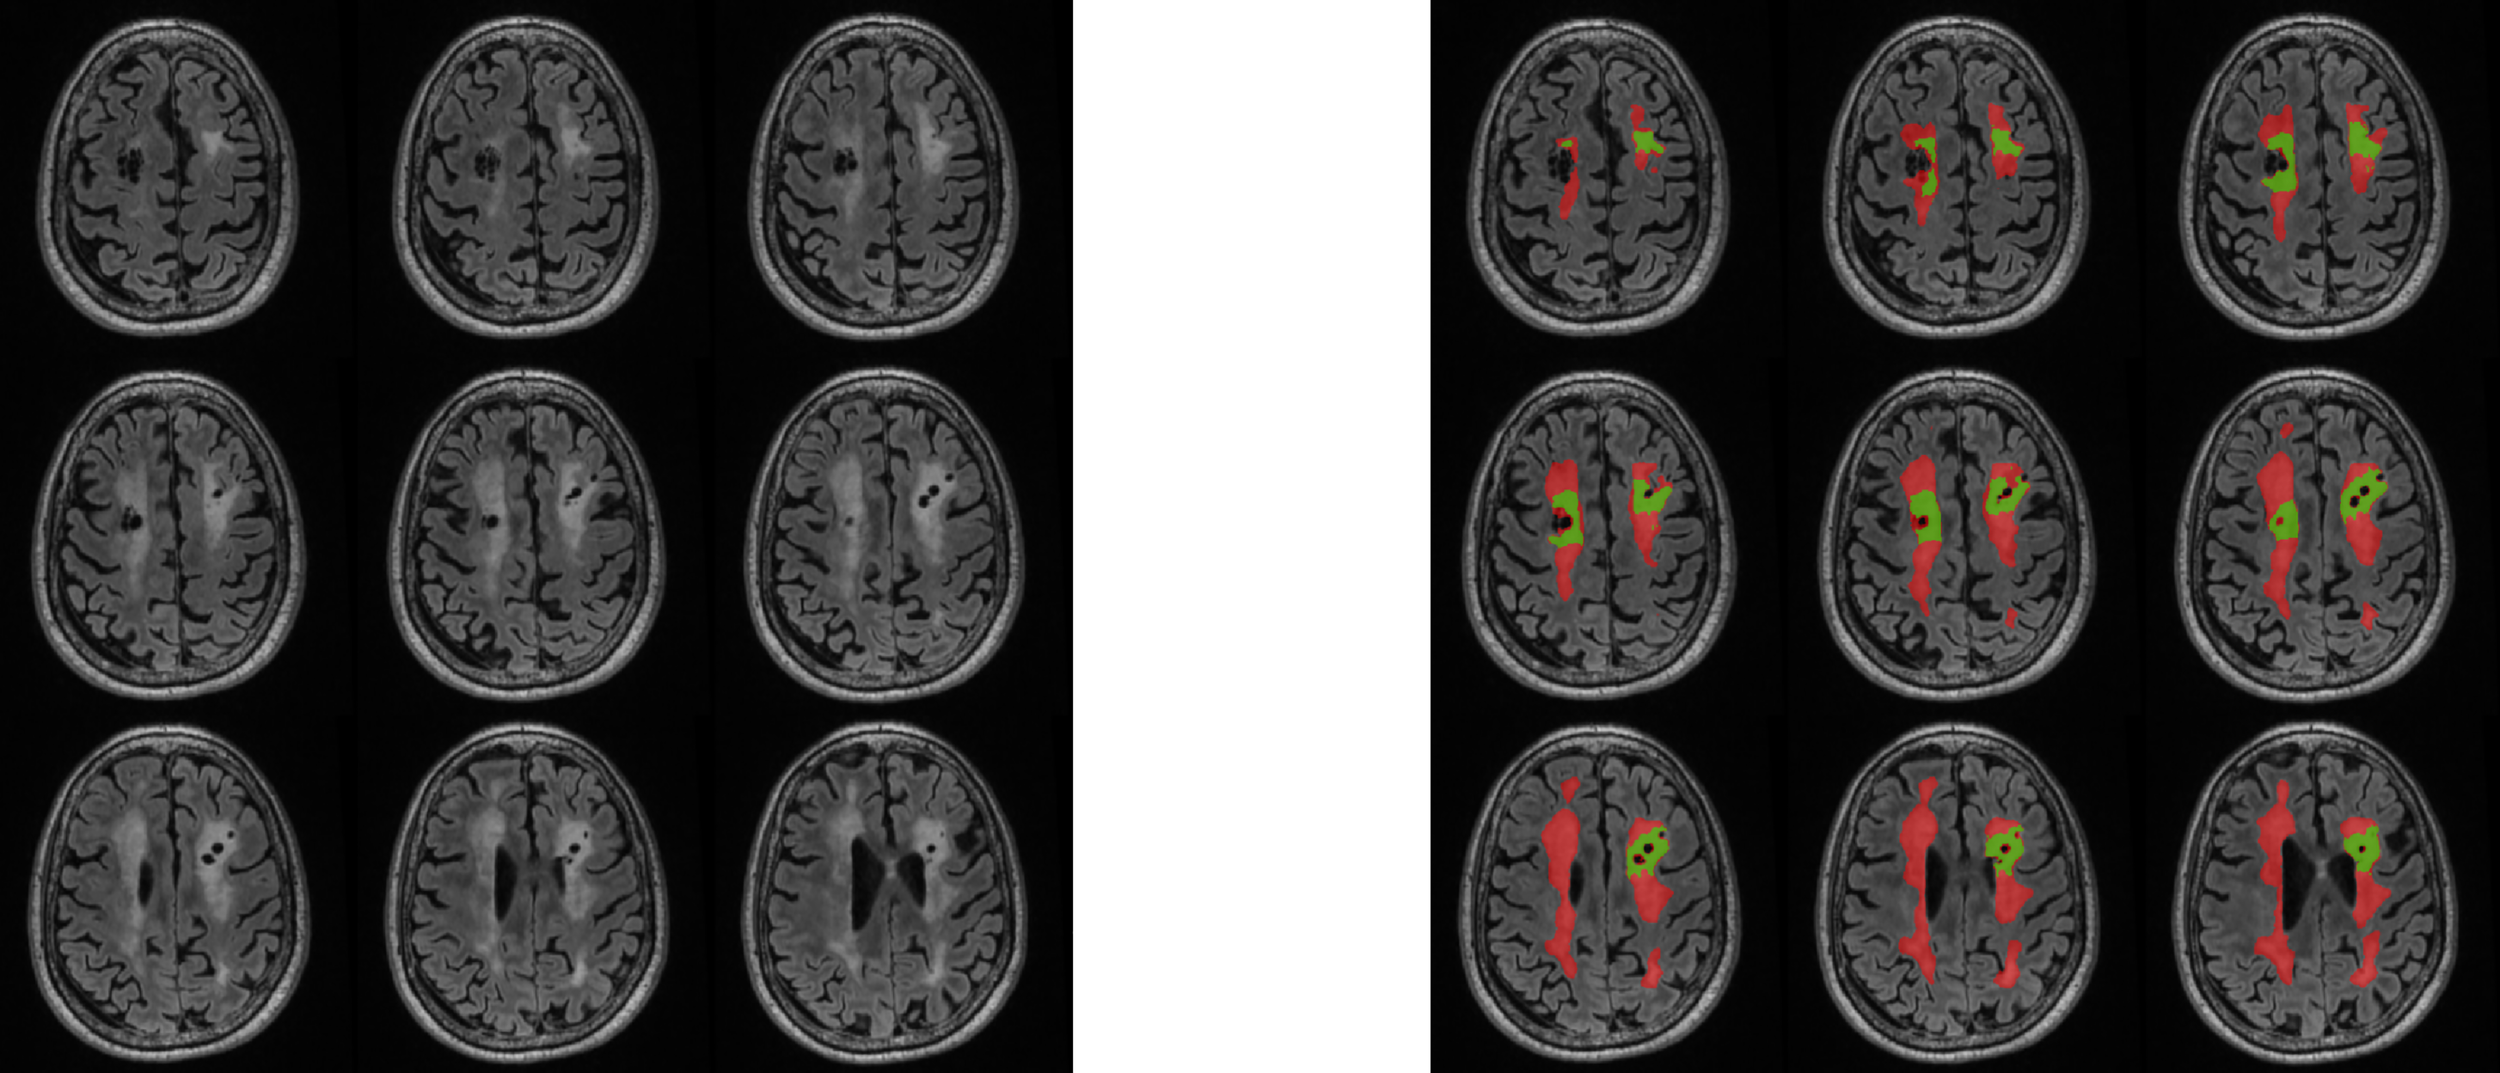

Figure 3

Visual representation of WML analysis. Imaging inclusive of manual T2-FLAIR white matter lesion segmentations with RT-induced (red) and non-RT-induced (green) labeling. RT, radiation therapy.

T2-weighted fluid-attenuated inversion-recovery (FLAIR) sequences were collected across study sites, with inter-site variability in two-dimensional and three-dimensional acquisitions. A previously described convolutional neural network with 3D U-net architecture (39, 40) was trained to identify abnormal FLAIR signal attributable to prior radiation, excluding abnormal FLAIR signal attributable to post-surgical changes or treated tumor tissue. Training data consisted of 246 expert manual segmentations of target FLAIR signal, which were initially segmented by a research specialist with several years of brain MRI segmentation experience and modified or verified by a board-certified neuroradiologist with 4 years of post-residency experience. Training data were independent of test data, noting that 9 of the MRIs used for training were from patients that were also included in the test set, but from MRIs obtained in different years from those in the test set. Training hyperparameters included a kernel size of 3 x 3 x 3, cross-entropy loss function, and an Adam optimizer with learning rate of 1 x 10−4, implemented in TensorFlow 2 (https://www.tensorflow.org) using the Python programming language. The network was trained for 110 epochs, with a batch size of 37 3D patches (96 x 96 x 96 mm each). The implementation was on a DGX-2 AI server (version 4.5.0; NVIDIA). The fully trained U-net was then applied to the patients in our cohort with available FLAIR sequences and neurocognitive assessments to detect and segment areas of abnormal FLAIR signal attributable to radiation treatment, and the volume of this abnormality was quantified.

Of the 41 patients with available T2 FLAIR imaging, 21 were male (51%; median age of diagnosis was 7 years [IQR 3. 10]; Table 1). Embryonal tumors were the most frequent tumor diagnosis (n = 19, 46%) with cerebellum/posterior fossa as the most common primary tumor location (n=17, 41%). Most patients (n=36, 88%) were treated with radiation therapy. Median age at initial neurocognitive assessment was 12 years (IQR 9, 17 and median time from diagnosis to initial neurocognitive testing was 6.0 years (IQR 3.0, 8.0; Table 2). In patients previously treated with radiation therapy, median time from radiation therapy to initial neurocognitive testing was 4.3 years (IQR 1.5, 6.4). Most patients (n=39; 95%) had measurable WML volumes identified by the convolutional neural network, of which the median volume was 1400 mm3 (IQR 349, 4590; Figure 3).